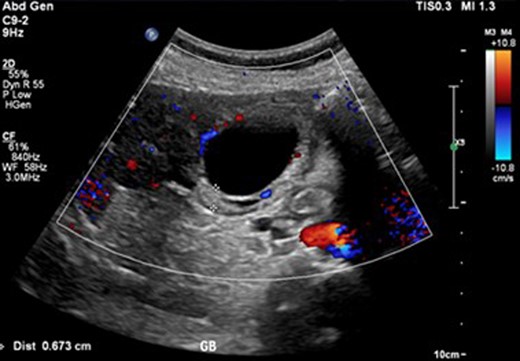

An abdominal ultrasound (Fig. 1) demonstrated a distended gallbladder with multiple subcentimeter gallstones. There was diffuse gallbladder wall thickening up to 7 mm and associated probe tenderness, consistent with cholecystitis. The common bile duct diameter measured up to 7.4 mm without any evidence of choledocholithiasis, thus did not require ERCP. However, the pancreas was not well visualized. A follow-up CT abdomen (Fig. 2) was performed, which demonstrated evidence of pancreatitis with moderate peripancreatic fat stranding without any features of complications including necrosis, abscess or pseudocyst.

Ultrasound image of cholecystitis demonstrating thickened gallbladder wall.